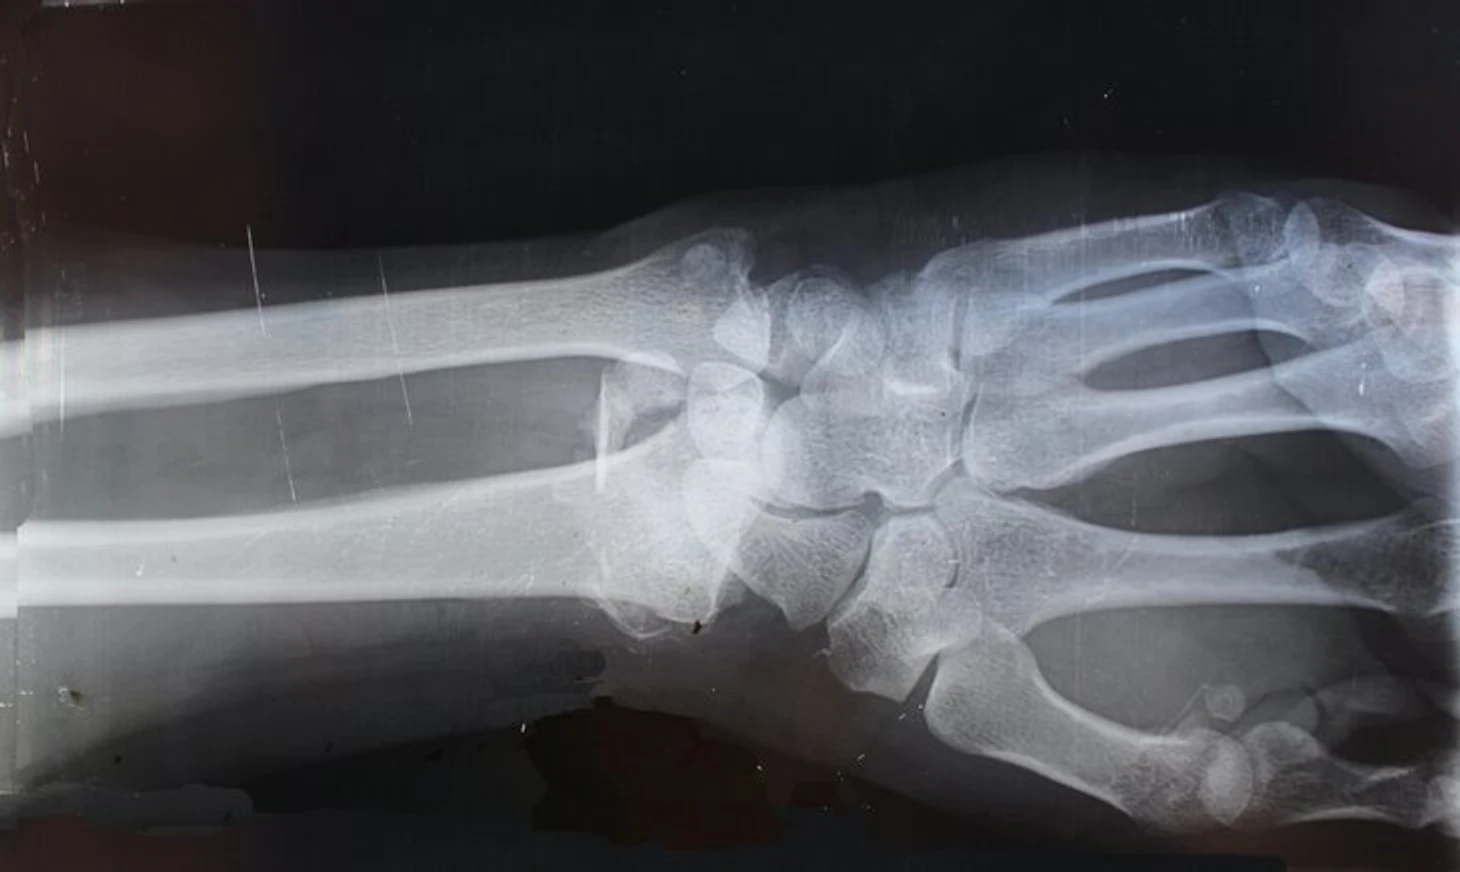

У людей моложе 18 лет главное – МРТ или рентген кисти руки. Сама процедура называется определением костного возраста – он указывает на уровень биологической зрелости человека. При исследовании врач сравнивает с данными, признанными нормой для возрастной группы.

У тех, кто старше 18 лет, возраст определяют по рентгенографии ключицы. Правда, технология ограничивает высокая лучевая нагрузка.